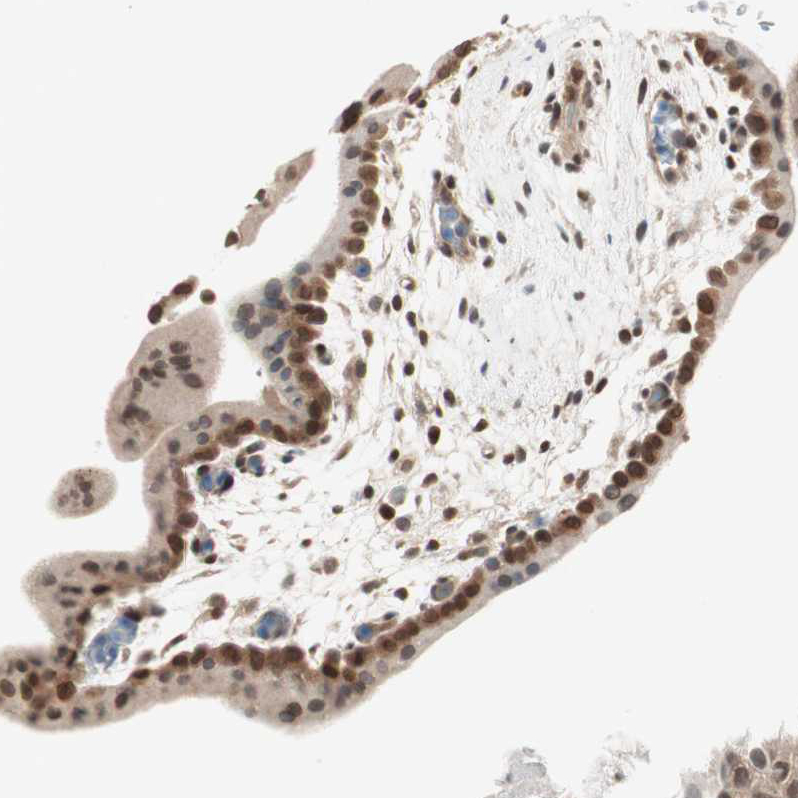

Immunohistochemical staining of human testis shows moderate to strong nuclear positivity in cells in seminiferous ducts.